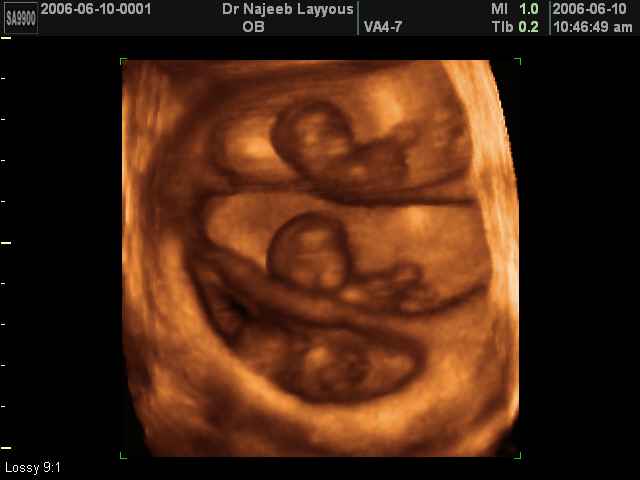

صور تربلتز اجنة لعيون سبوعة

شوفوا كيف منفعصين مساكين